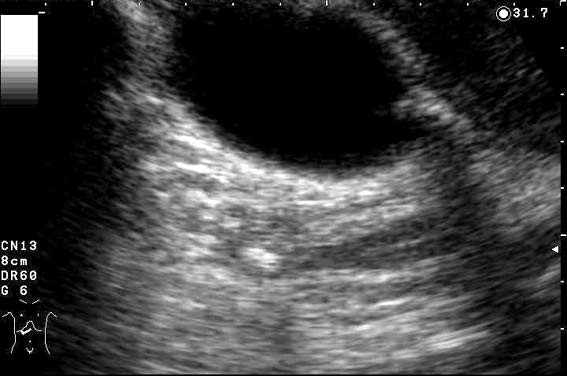

Пациент с невыраженной желтухой и приступом накануне.

Ваше заключение?

Инга писал(а):Холедохолитиаз

Я бы еще добавил низкое впадение цистикуса.

Холедохолитиаз.

Про уровень слияния протоков не скажу.